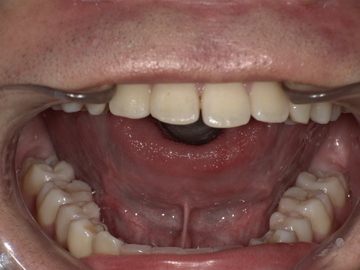

Before

舌小帯が短く、舌先を上あごまで十分に持ち上げることができません。